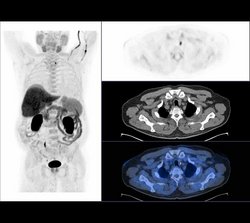

Cholin PET/CT zur Lokalisationsdiagnostik:

NSD-Adenom am caudalen Pol der Schilddrüse links.

Bild li. Cholin PET: fokale Merspeicherung am caudalen Pol der Schilddrüse links

Bilder re: CT kleine RF am caudalen Pol der Schilddrüse links

Untersuchungsergebnisse: Sonografisch lässt sich eine echoärmere Formation dorsal des unteren Schilddrüsenpoles li abgrenzen, nachfolgende NSD-Szintigrafie (MIBI) nicht eindeutig, eine Cholin-PET/CT Untersuchung zeigt eine eindeutige Mehrspeicherung li kaudal dorsal des unteren Schilddrüsenpoles. (siehe Bild li.)